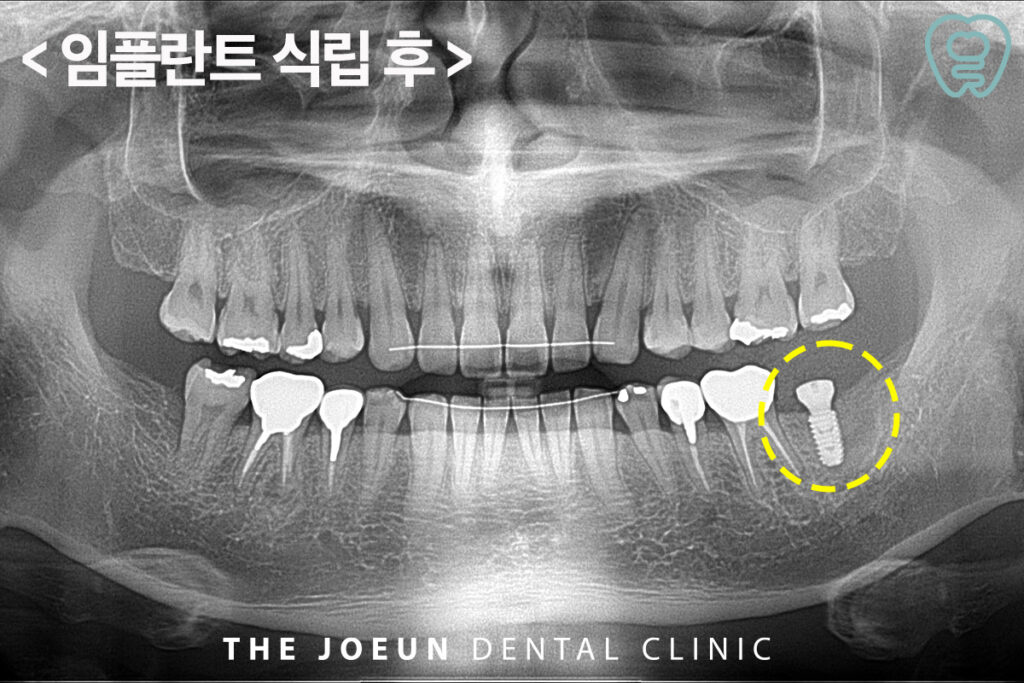

이후 임플란트 식립을 진행하였는데요.

수술 후 관리 역시 성공률을 결정하는 핵심 요인으로 흡연은 혈류 공급을 저하시켜 이식 부위 회복을 방해하고, 골형성을 저해해 실패 위험을 높일 수 있습니다. 또한 수술 직후에는 열 자극이 강한 샤워나 운동을 피해야 하며 단단한 음식 섭취를 제한해 안정화를 도와야 합니다. 침을 뱉는 행동도 혈류 흐름을 자극할 수 있어 삼키는 편이 회복에 유리하고 장기적인 관점에서는 정기 검진과 위생 관리가 필수적입니다.